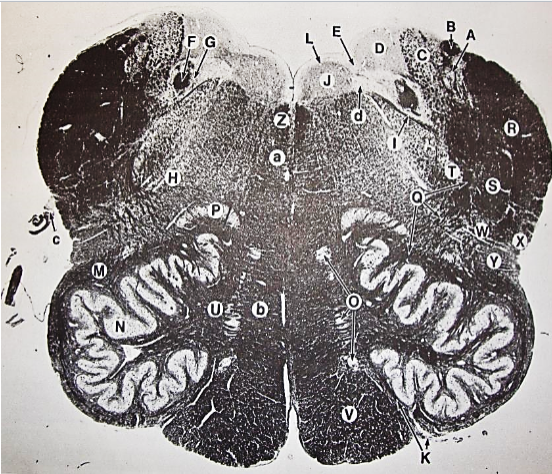

A

Lateral Cuneate nucleus

B

dorsal external arcuate fibers

C + D collectively

vestibular nuclei

C + D collectively

vestibular nuclei

E

dorsal motor nucleus of vagus nerve

F

solitary fasciculus

G

solitary nucleus

H

nucleus ambiguous

I

fascicles of glossopharyngeal nerve

J

hypoglossal nucleus

K

fascicles of hypoglossal nerve

L

dorsal longitudinal fasciculus

M

central tegmental tract

N

inferior olivary nucleus

R

inferior cerebellar peduncle

S

spinal trigeminal tract

T

spinal trigeminal nucleus

U

ventral trigeminothalamic tract

V

pyramidal (corticospinal) tract

W

rubrospinal tract

X

anterior spinocerebellar tract

Y

spinal lemniscus

Z

medial longitudinal fasciculus

a

tectospinal tract

b

medial lemniscus

c

vagus nerve

d

inferior salivatory nucleus

A + B collectively

vestibular nuclear complex

D

solitary fasciculus

E

solitary nucleus

F

nucleus ambiguous

G

fascicles of glossopharyngeal nerve

H

spinal trigeminal tract

I

spinal trigeminal nucleus

J

ventral trigeminothalamic tract

K

central tegmental tract

L

interior olivary nucleus

O

inferior cerebellar peduncle